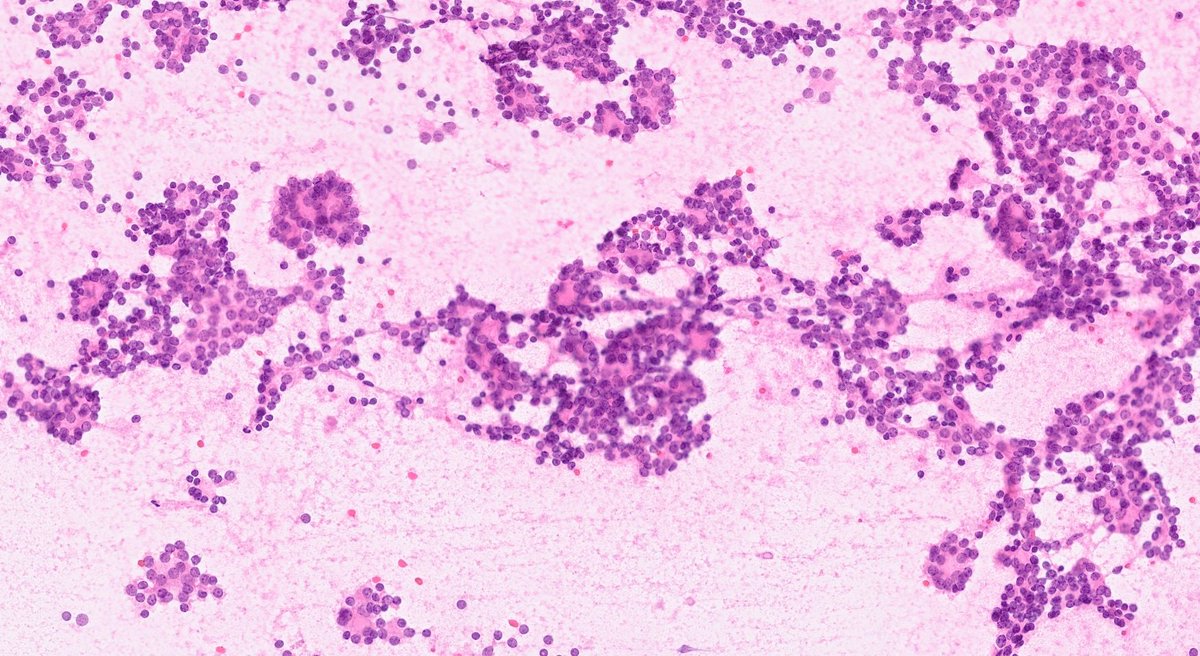

FNA from a 45yo man with a history of pheochromocytoma, what is your interpretation? A) Papillary thyroid carcinoma B) Follicular Neoplasm C) Medullary thyroid carcinoma D) Metastatic pheochromocytoma #CytoPath #EndoPath #PathTwitter #Pathology

A) Papillary thyroid carcinoma

B) Follicular Neoplasm

C) Medullary thyroid carcinoma

D) Metastatic pheochromocytoma